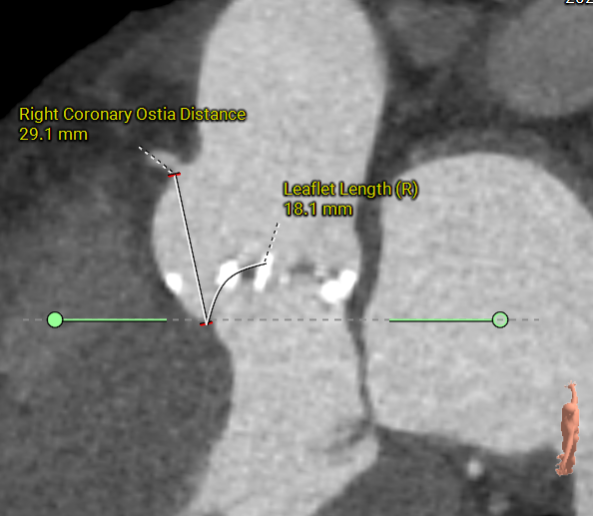

右冠开口高26.9mm

右冠开口高14.8mm